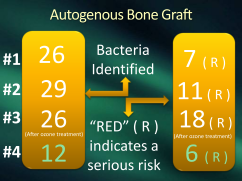

Grafts should be considered like transplants

not just inserted without a glance

So try for autogenous, like a piece of torus

should be accepted for its quite porous

My body will surely accept them

for I have plenty of glycoleptin

Blood clots are far better instead

delicate bone cells will always die

In 30 seconds with no blood supply

Why not pull teeth and place implants